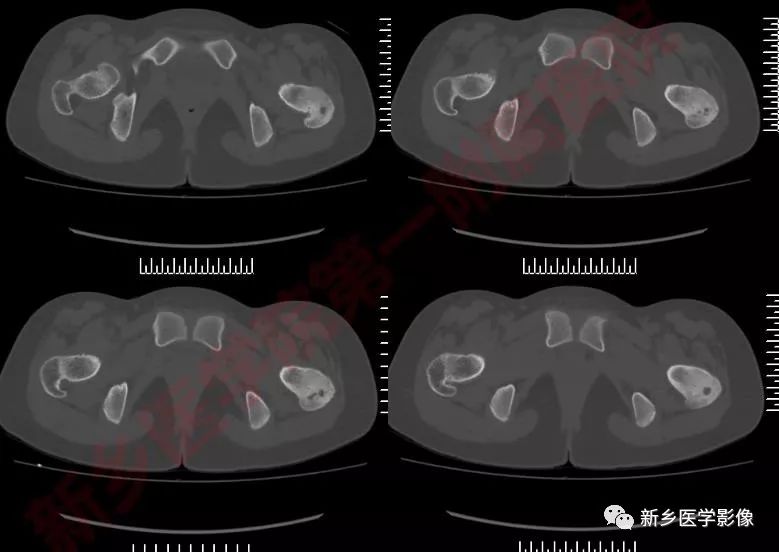

影像表现:

骨样骨瘤的影像学表现具有特征性,其典型的表现为:

瘤巢所在部位的骨质破坏及周围不同程度的骨质硬化,还可伴有骨膜反应、周围软组织或相邻关节的肿胀。

X线片上可分为皮质型,松质型和骨膜下型。

其中皮质型占70%,最常见,多见于长骨骨干。瘤巢靠近骨皮质内面,有小的透射线区域,周围是致密骨,若位于皮质内,则硬化环更明显。反应性增生硬化明显时,可遮盖瘤巢。

松质型:最常见于股骨颈,其次是手足的小骨和椎体,瘤巢位于骨端或不规则骨,周围硬化不明显,可仅有骨硬化边,病灶周围常无 新骨形成,但有密度增加的骨环包绕病灶。

—CT/平片:低密度,但内部的骨组织表现高密度

CT/平片上,“瘤巢”周围多出现反应性骨质增生硬化:松质骨增生硬化或骨膜反应